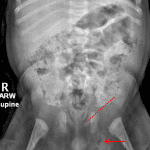

Age: 5 months

Sex: Male

Indication: Spitting up, decreased bowel movements

Findings

- Gas-containing left inguinal hernia

- Nonobstructive bowel gas pattern

- No evidence of free intraperitoneal air

- No abnormal intraabdominal mass effect or calcification

- Normal appearance of the chest

- Mild irregularity of the proximal femoral and humeral metaphyses bilaterally

Diagnosis

- Inguinal hernia

- Rickets

Gas-containing left inguinal hernia without evidence of bowel obstruction.

No evidence of free intraperitoneal air.

No abnormal intraabdominal mass effect or calcification.

Normal appearance of the chest.

Mild irregularity of the proximal femoral and humeral metaphyses bilaterally, which could relate to rickets. Consider dedicated wrist radiographs for further evaluation.